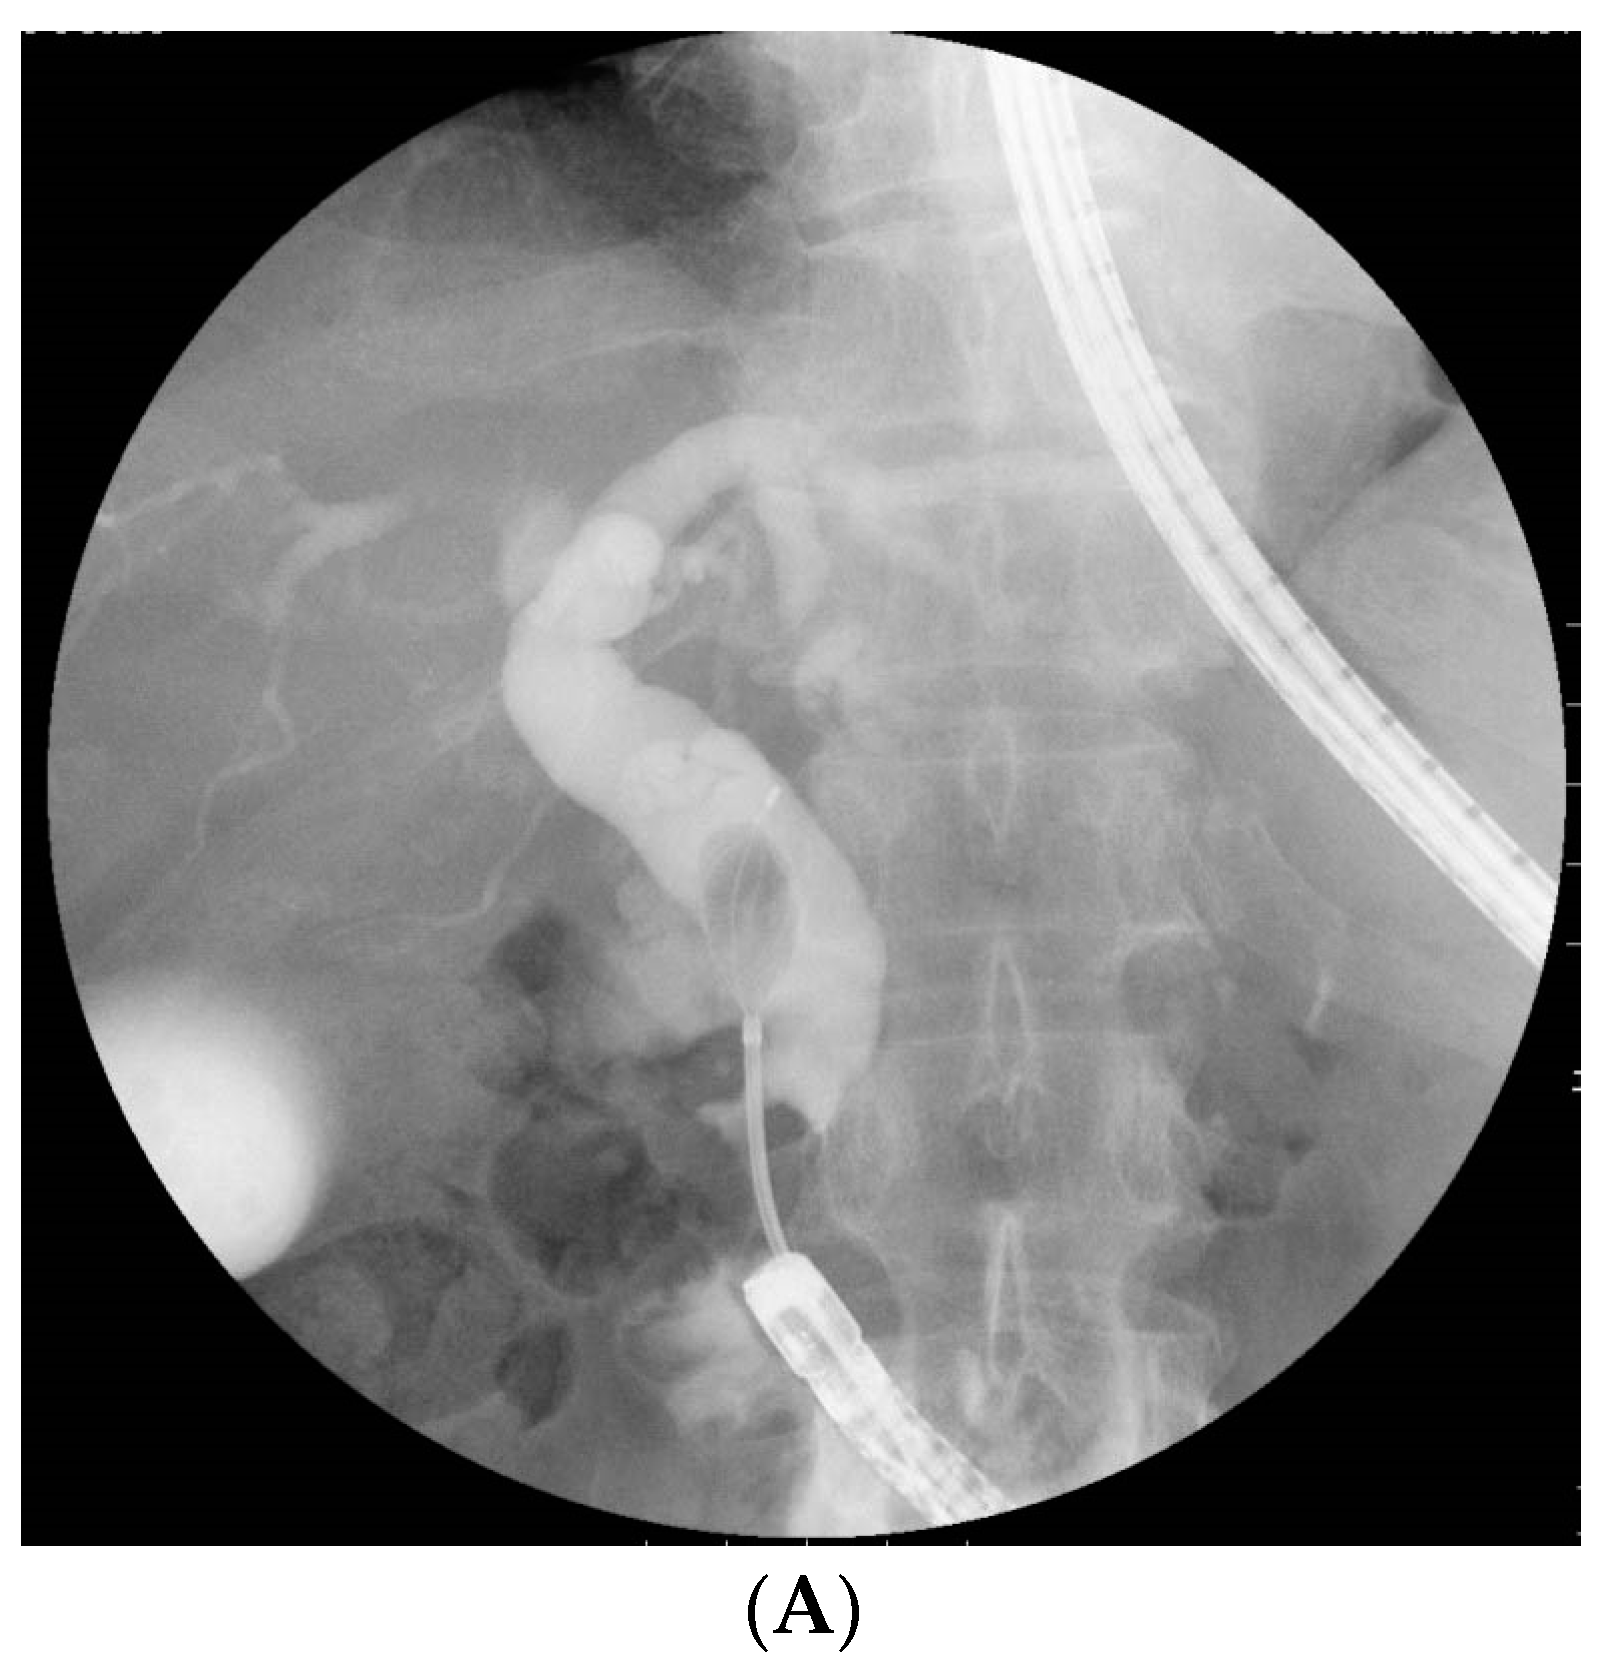

2.3. BE-ERCP Procedure

3.4. Biliary Intervention and Complete CBD Stone Extraction in an Initial BE-ERCP